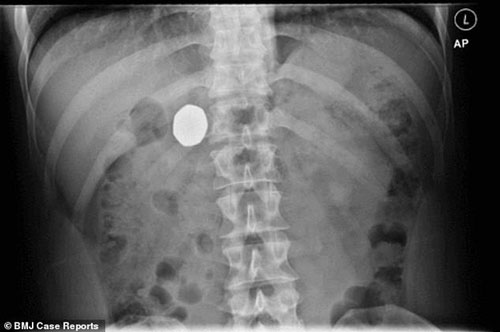

Sau hành động dại dột này, người đàn ông 29 tuổi (hiện vẫn chưa xác định được danh tính) đã bị nôn dữ dội, đẩy được đồng 20 xu ra ngoài. Tuy nhiên, do kích thước lớn hơn, đồng 50 xu vẫn bị mắc kẹt trong cơ thể người đàn ông này 10 tuần sau đó.

Hai tuần sau khi nuốt đồng xu vào bụng, người đàn ông này đã tới phòng cấp cứu của Bệnh viện hạt Hereford vì bị những cơn đau bụng dữ dội hành hạ. Bệnh nhân đã thành thật kể cho bác sĩ tất cả những gì đã xảy ra, đồng thời cho biết mình đã nôn đồng 20 xu ra ngay sau khi uống hết ly bia.

Các bác sĩ phát hiện đồng 50 xu đã đi vào niêm mạc dạ dày của bệnh nhân 29 tuổi. Ảnh: AP |

Sau khi thăm khám, các bác sĩ xác định đồng 50 xu vẫn đang nằm trong cơ thể của bệnh nhân. Bệnh nhân được khuyên tiếp tục chế độ ăn uống bình thường và quay lại bệnh viện sau 1 tuần nếu như không phát hiện ra đồng xu trong phân của mình.

Một tuần sau, anh này quay lại bệnh viện và cho biết đồng xu vẫn chưa được đẩy ra ngoài, tuy nhiên các triệu chứng đau bụng hay nôn mửa đã giảm một cách đáng kể.

Bác sĩ Yih Chyn Phan và một nhóm các chuyên gia sau đó tiến hành siêu âm và phát hiện đồng 50 xu đã đi vào niêm mạc dạ dày của bệnh nhân. Đây cũng là trường hợp bệnh nhân đầu tiên nuốt phải tiền xu khiến nó di chuyển tới niêm mạc dạ dày.

Cho tới thời điểm hiện tại, các bác sĩ vẫn khuyên bệnh nhân không nên quá lo lắng và chờ đợi đồng xu sẽ được đẩy ra ngoài theo cách tự nhiên nhất. Lý do là bởi các chuyên gia cho biết việc phẫu thuật để lấy đồng xu ra ngoài sẽ gây ra nhiều rủi ro hơn so với việc để đồng xu ở bên trong cơ thể của bệnh nhân.